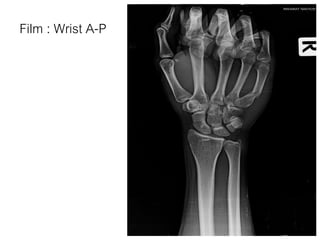

Film : Wrist A-P

• Close fracture shaft of 5th metacarpal bone(Proximal part) of

Right hand